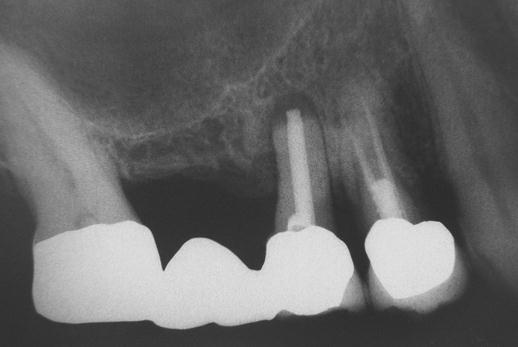

Sinus lift

Nejčastější oblastí pro doplnění kosti je čeleni dutina horní čelisti.

Tento výkon se nazývá sinus lift - aplikace kostního granulátu do čelistní dutiny

Při ztrátě molárů a premolárů v horní čelisti a jejich náhradě implantáty se často setkáváme s nedostatečnou vertikální nabídkou kosti pod čelistní dutinou, často doprovázenou i nedostatečnou horizontální nabídkou a sníženou kvalitou kosti

(v oblasti 2. premoláru v 50%, v oblasti moláru až v 80% případů nedostatečná kostní nabídka)

Od roku 1985 je tento problém řešen augmentační operací nazývanou sinus lift.

Jedná se o vyzvednutí membrány, která čelistní dutinu vystýlá, pod vyzvednutou membránou vznikne kapsa, kam se umístí augmentační materiál, do kterého se zavedou implantáty.

Vhojení implantátů se při této operaci prodlužuje na 6-12 měsíců.